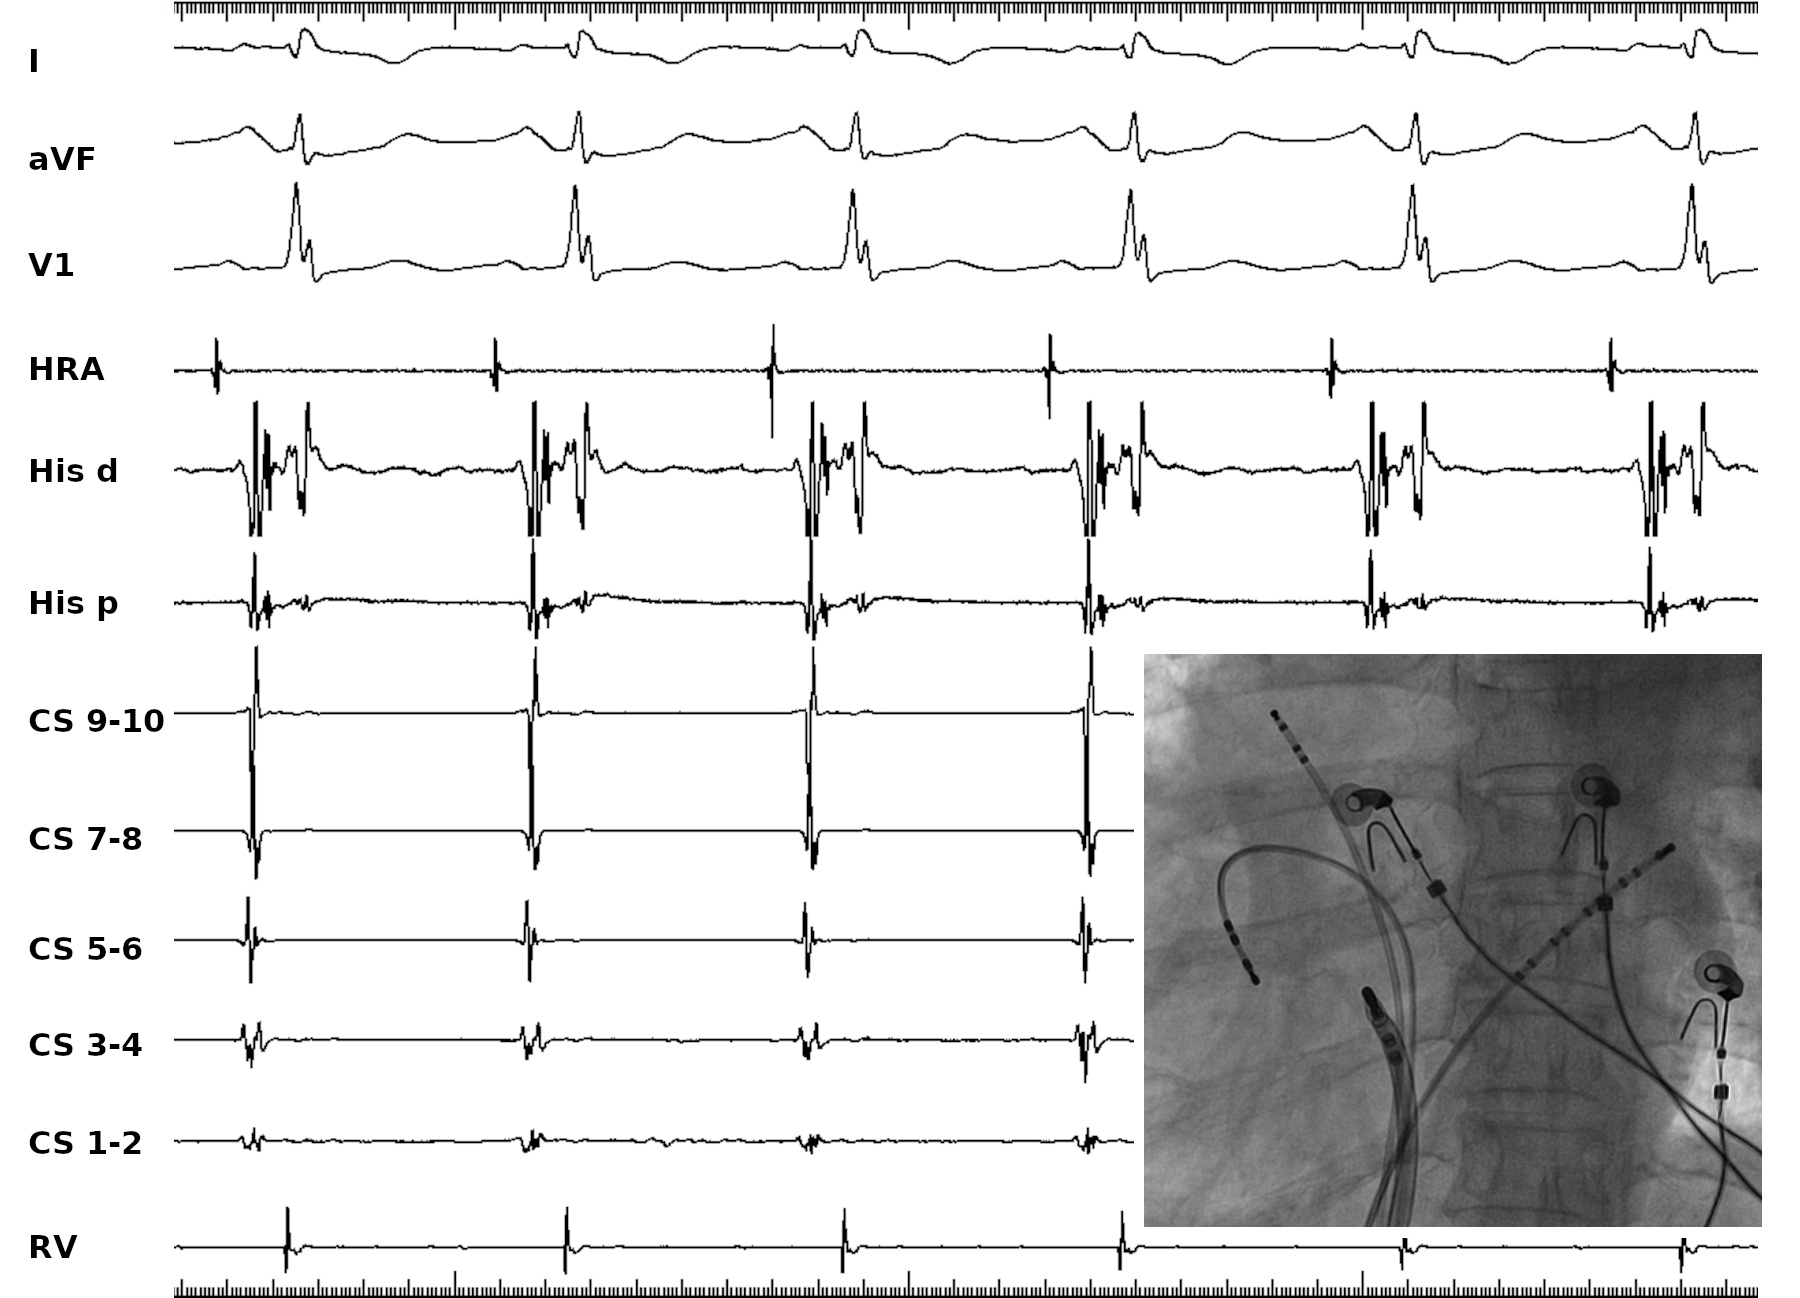

Anterior His during sinus rhythm

sinus_ant_his.jpg